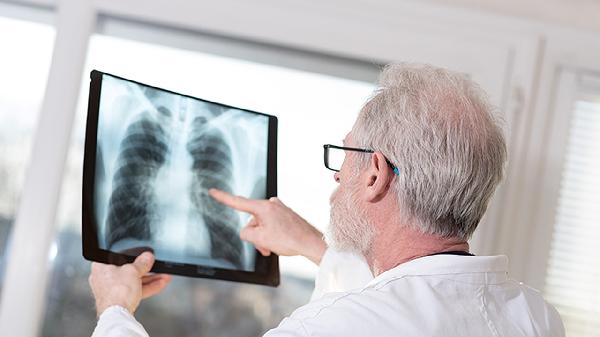

胸部X线可显示肺结核典型病变,如上肺野浸润影、空洞形成或纤维钙化灶。早期表现为斑片状阴影,进展期可出现干酪样坏死伴透亮区。该检查对粟粒型肺结核诊断敏感性较低,需联合CT检查。检查时需去除金属物品,孕妇应告知医生并评估必要性,必要时采用铅防护措施。